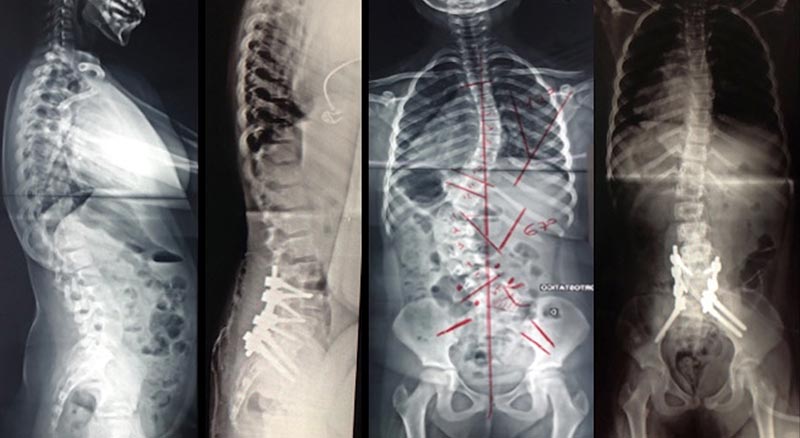

- Osteotomias: objetivo: correção em um único estágio. Problemas: dificuldade técnica riscos em relação a perda sanguínea, tempo cirúrgico, dano neurológico. Exemplos: Vertebrectomias: tipo 1: egg-shell, tipo 2: hemivertebrectomia, tipo 3: vertebrectomia total. Vertebrectomia total: remove toda a vértebra, inclui disco acima e abaixo; indicada se curva aguda e fixa acima de 100 graus (exemplo figura 11).

Figura 11. Ressecção de hemivertebra